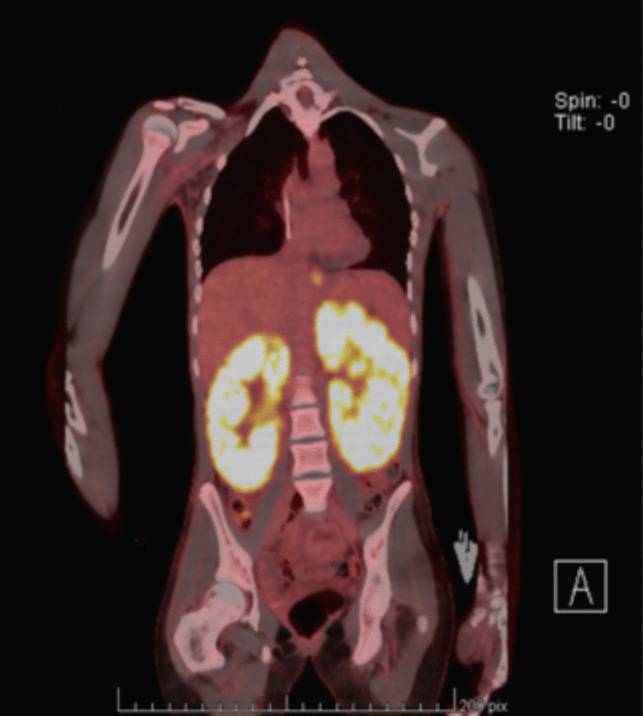

Methods: We present a rare case of primary bilateral renal diffuse large B-cell lymphoma in a teenage girl presenting with kidney failure (eGFR of 7 ml/min/1.73 m2), proposing a practical approach to optimize chemotherapy on kidney replacement therapy. We discuss diagnostic methods, the management and adjustment of chemotherapy and hyperhydration protocols, and the tailoring of highly efficient hemodiafiltration sessions to grant sufficient drug exposure while avoiding drug accumulation and toxicity in the context of kidney failure.

Results: This approach permitted a substantial reduction of chemotherapy adverse effects while inducing remission and partial recovery of kidney function in our patient, with hemodialysis discontinuation after 6 months, and an eGFR that had improved to 28 ml/min/1.73 m2 at 12 months.